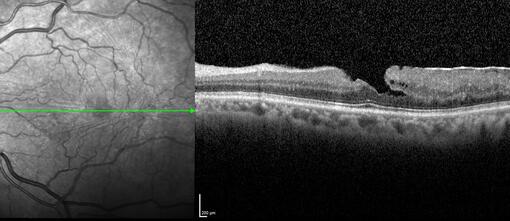

El doctor Juan Manuel Cubero hace un repaso integral del destacado papel de la tomografía de coherencia óptica en la evaluación de casos de desprendimiento de vítreo, síndromes de tracción vítreorretiniana, desprendimiento de retina, y la aplicación intraoperatoria de la OCT

Clase 20 - Signos clave en patología traccional vítrorretiniana

Clase 21 - Desprendimiento de vítreo y desprendimiento de retina